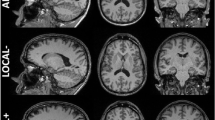

The hippocampus has a critical role in many common disease processes. Currently, routine 3 Tesla structural MRI is a mainstay of clinical diagnosis. The goal of our study is to evaluate the normal variability in size and/or conspicuity of the hippocampal subcomponents in routine clinical 3 Tesla high-resolution T2-weighted images to provide a basis for better defining pathological derangements. Additionally, we utilize diffusion data acquired from a 17.6 Tesla MRI of the hippocampus as a benchmark to better illustrate these subcomponents.

The hippocampus was retrospectively assessed on 104 clinically normal patients undergoing coronal T2-weighted imaging. The conspicuity of the majority of hippocampal subcomponents was assessed in each portion of the hippocampus. Additionally, easily applicable cross-sectional measurements and signal intensities were obtained to evaluate the range of normal, as well as inter- and intra-subject variability.

The normal range of cross-sectional measurements of the hippocampal subcomponents was calculated. There was minimal side-to-side variability in cross-sectional measurements of hippocampal subcomponents (< 5%) with the exception of the subiculum (R>L by 8.3%) and the CA4/DG (R>L by 5.8%). The internal architecture showed high variability in visibility of subcomponents between different segments of the hippocampus.

Confident clinical assessment of the hippocampus requires a thorough knowledge of hippocampal size and signal, but also the internal architecture expected to be seen. The data provided in this study will provide the reader with vital information necessary for distinguishing a normal from abnormal exam.